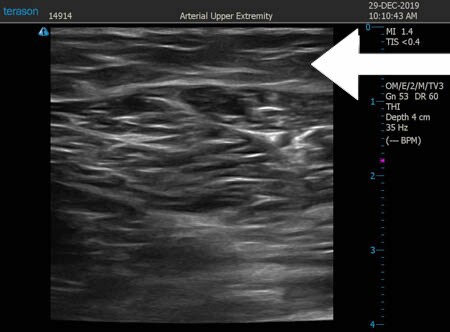

いつものように3Dタッチビュー(超音波)で

皮下脂肪層を評価してみましょう。

右ふくらはぎ

上の画像の部分の皮下脂肪層をつまんでみましょう。

ふくらはぎは一般的に筋肉質なもの。

今回の患者様も筋肉質ではあったものの

皮下脂肪もそれなりに付いていましたので

徹底的に根こそぐことで

患者様には満足していただこうと思いました、。